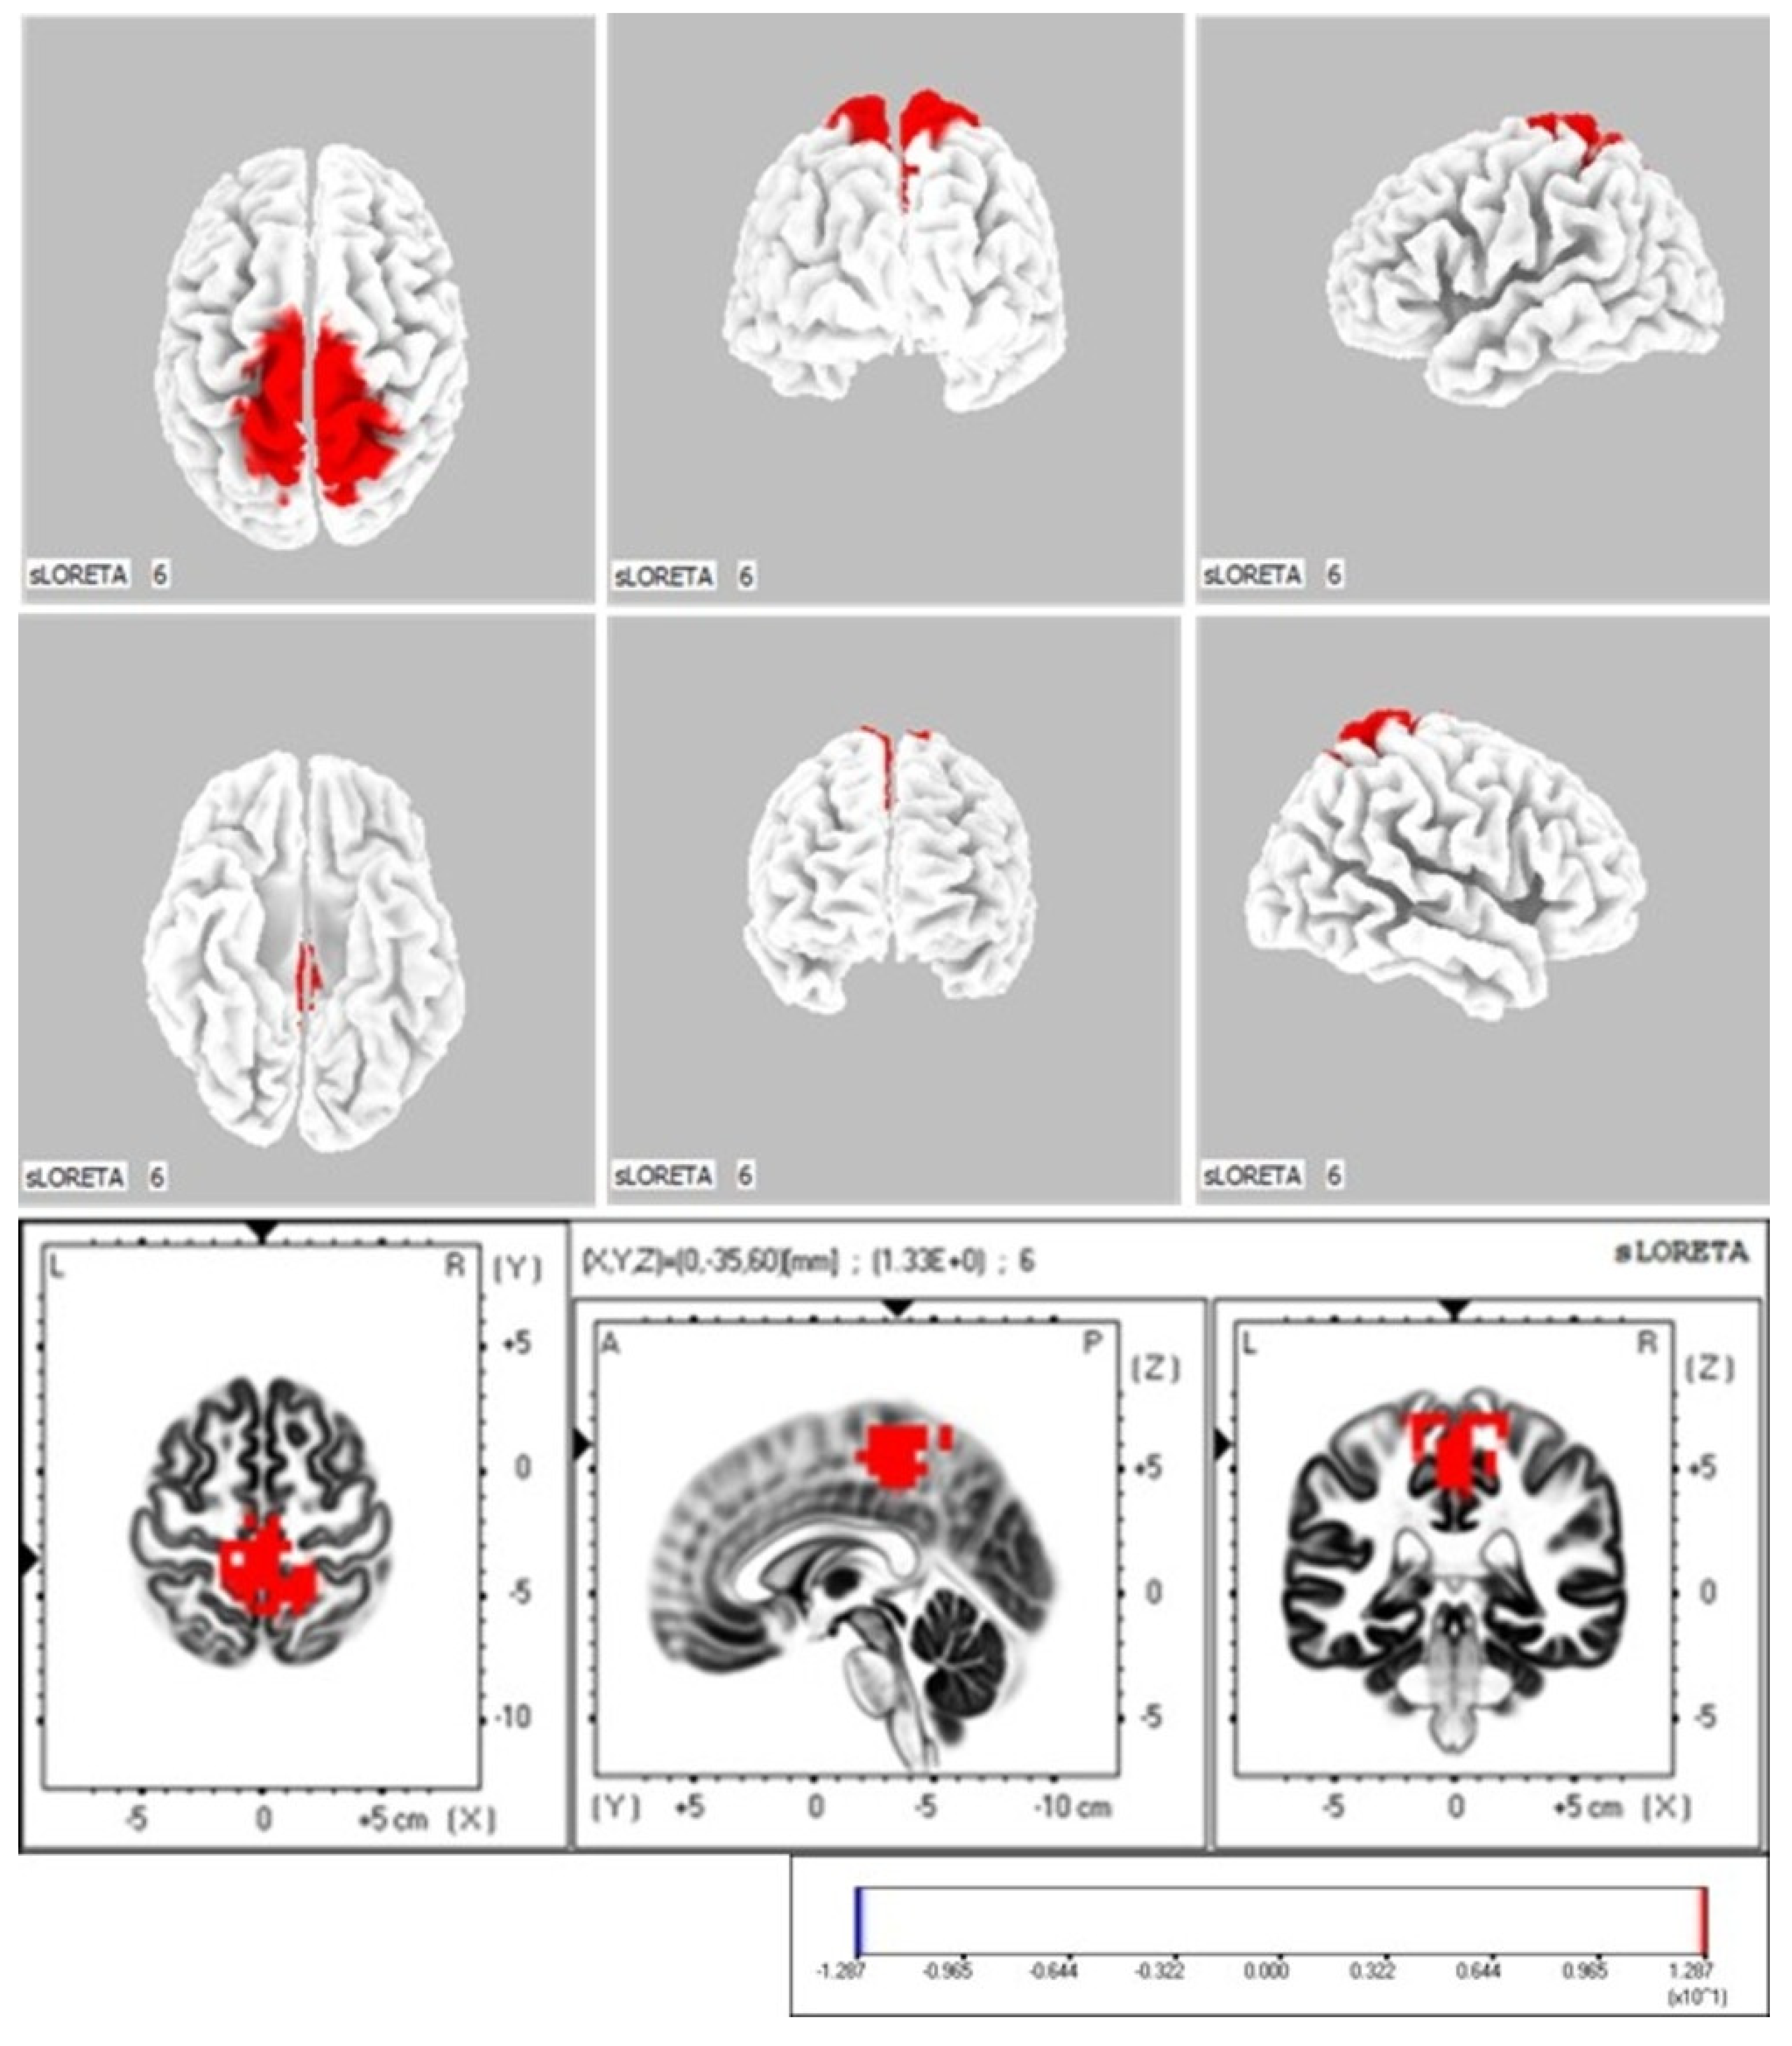

3.1.2. Comparison of Neurophysiological Indicators in the Active Ankle Dorsiflexion Movement Task